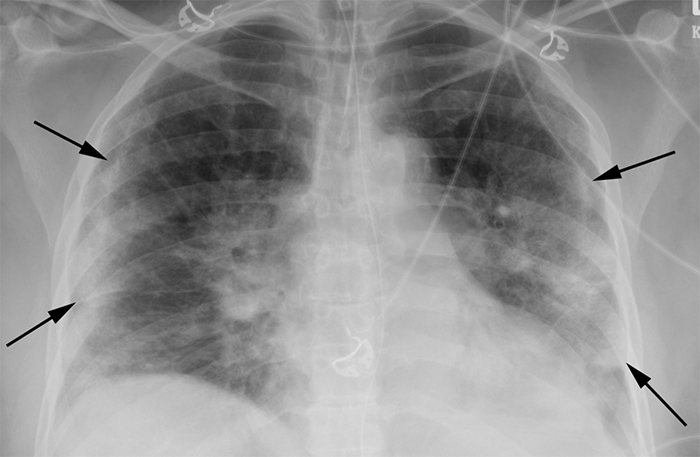

chesy x-ray suggesting COVID

“The presence of patchy and/or confluent, band-like ground glass opacity or consolidation in a peripheral and mid-to-lower lung zone distribution on a chest radiograph is highly suggestive of SARS-CoV-2 infection and should be used in conjunction with clinical judgment to make a diagnosis,” says Bradley Spieler MD, Associate Professor of Diagnostic Radiology and Vice Chairman of Research in the Department of Radiology at LSU Health New Orleans School of Medicine.

“The chest radiograph, while low in sensitivity, can indicate COVID-19 in patients whose radiographs exhibit characteristic COVID-19 findings, when used in concert with clinical factors,” adds John-Paul Grenier, MD, an LSU Health New Orleans Radiology Resident. “While not a substitute for RT-PCR virus tests or Chest CT, radiographs could provide a rapid, cost-effective diagnosis of COVID-19 in a subset of infected patients during the COVID-19 pandemic. The utility of this technique is described in the context of known disadvantages of RT-PCR, considered the gold standard in COVID-19 diagnosis, and Chest CT, which is currently not recommended for COVID-19 diagnosis. “